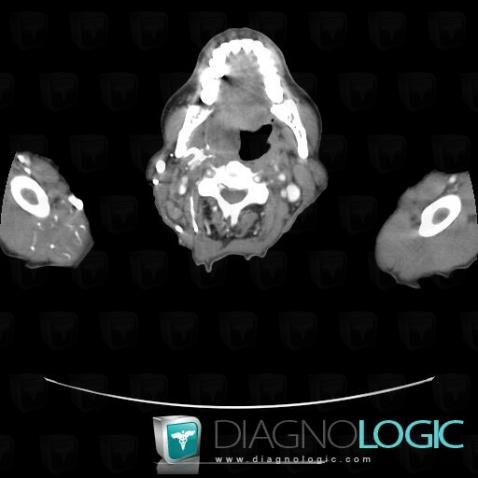

Lymphoma, Oropharynx / Floor-mouth, CT

Here is the specific information in the key image above:

- Diagnosis Lymphoma, Location(s) Oropharynx / Floor of mouth, with gamuts Oropharynx or floor of mouth non cystic mass